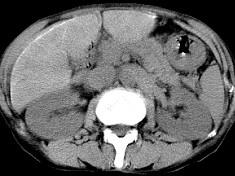

问题 男,40岁有血吸虫感染史,腹胀不适,食欲减退,CT扫描所见如图,最可能的诊断是 ( )

选项 A.肝炎后肝硬化 B.血吸虫后肝硬化 C.酒精性肝硬化 D.胆汁性肝硬化 E.脂肪肝

答案 B